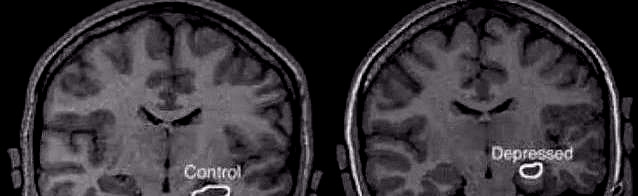

大脑海马体体积的大小不同

正常大脑(左)与抑郁症患者大脑(右)海马体大小对比

重度抑郁患者,他们的脑前额叶-边缘系统(杏仁核、海马等)中灰质密度和分数低频振荡幅度(fALFF)显著低于健康人。

海马体是我们大脑当中负责记忆和认知功能最核心的区域,也涉及到一些情绪功能。

如果治疗不彻底,或者缺乏有效治疗,海马体就会越来越小。